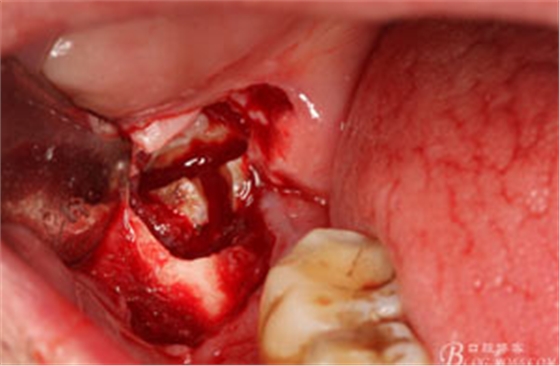

圖12. 先取出48牙冠

圖13.從頰側(cè)和舌側(cè)兩個(gè)方向用挺。挺出牙根